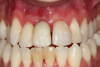

Fig 12. Six months after cementation.

Figure 12